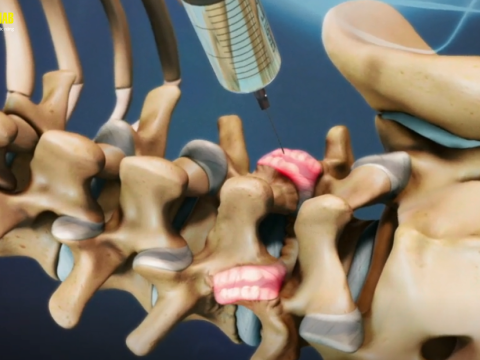

Tiêm cột sống